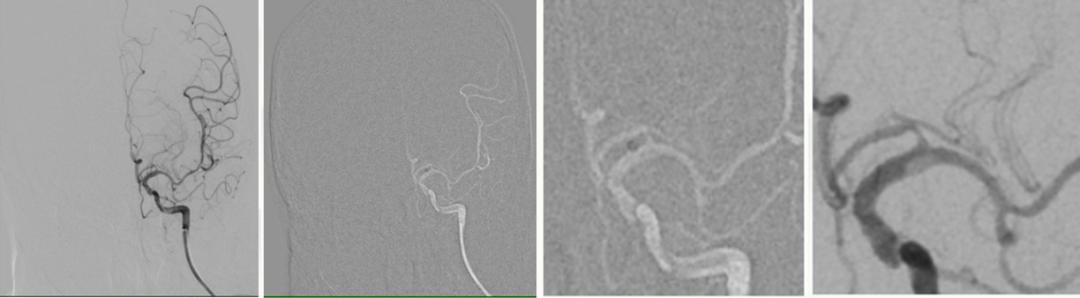

影像诊断

病历夹什么径技·第151期|串联营病历夹:京广连营_https://www.jmylbn.com_新闻资讯_第46张

病历夹什么径技·第151期|串联营病历夹:京广连营_https://www.jmylbn.com_新闻资讯_第47张

病历夹什么径技·第151期|串联营病历夹:京广连营_https://www.jmylbn.com_新闻资讯_第48张

<<滑动查看下一张图片>>

结论:DWI高信号,患者无明显症状(额颞梗死),前交通动脉开放,右侧大脑中动脉显影,考虑右侧颈内动脉慢性闭塞,不除外急性闭塞及急性血栓栓塞。患者于入院后约11小时左右再次出现左侧肢体无力症状,给予静脉替罗非班8ml推注,6ml/小时持续泵入,30分钟症状无缓解。